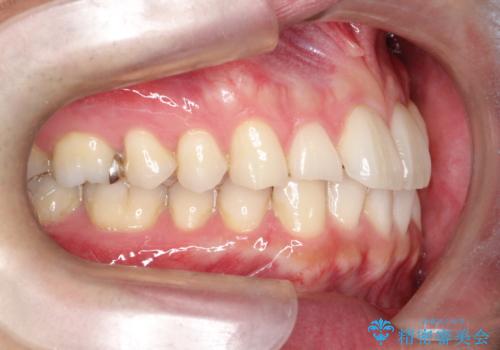

- 前歯の凸凹と顎の偏位を主訴に来院されました。

下顎の偏位を認めましたが、外科矯正を希望されなかったためできる範囲で顎の偏位を治すことができるよう治療を行なっております。

治療開始前に、下顎位の評価をおこなうことで、完成度の高い治療を行うことができました。